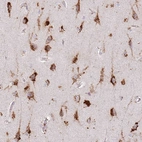

Immunohistochemical staining of human cerebral cortex shows strong cytoplasmic granular positivity in neurons.